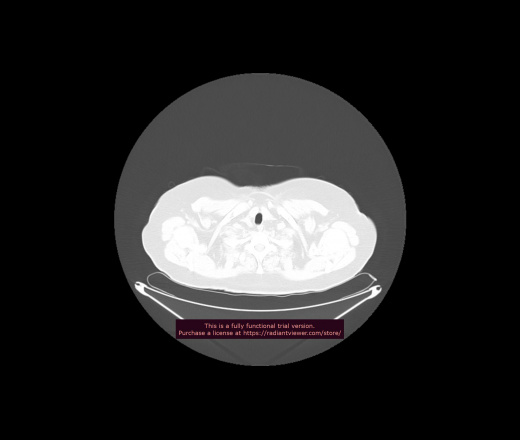

Уважаемые коллеги, если имеется интерес, сможете ли Вы спрогнозировать дальнейшее +-одинаковое течение процесса у 4 данных разных пациентов? Зацепиться где-то можно очень просто, где-то нельзя.